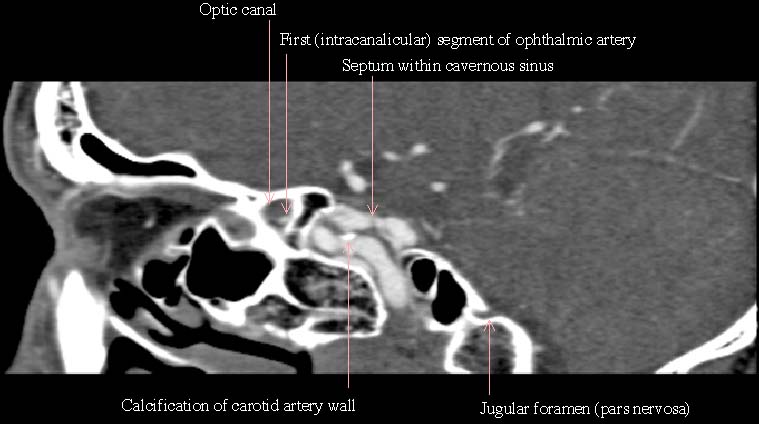

0.5mmx4, Pitch 3.0, 60mm, 20 seconds, 150mAs